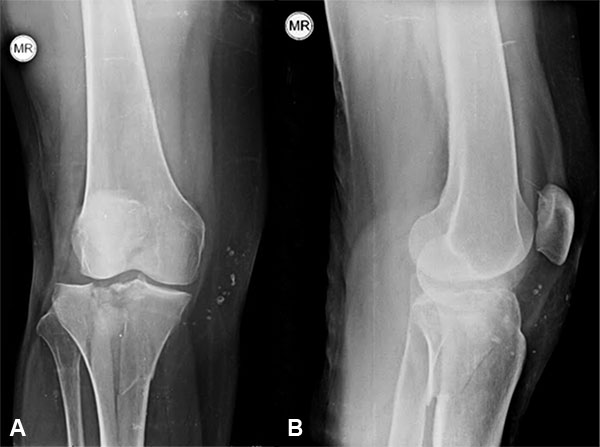

El diagnóstico se realizó siguiendo los hallazgos clínicos, radiográficos, de la tomografía computada o la RMN según el caso (figs. 1 a 7).

Figura 1: Masculino, 48 años, Schatzker 1.

Figura 2: Mismo paciente imagen TAC.

Figura 3: Control post quirúrgico al año.